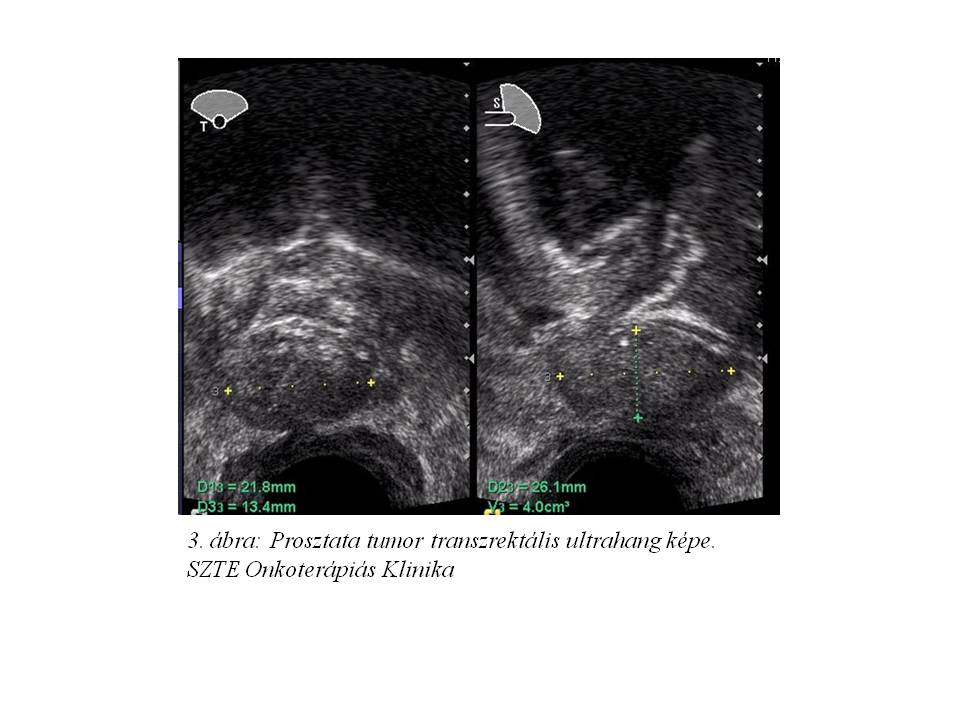

Urológiai konzílium és manuális prosztata vizsgálat történt, mely porckemény terimét véleményezett. Transzrektális ultrahang vizsgálat a prosztataágynak megfelelően egy 22 x 26 x 13 mm nagyságú, inhomogén lágyrész képletet írt le, baloldalon 8 mm-es, körülírtabb echoszegény területtel (3. ábra). Az elváltozásból vastagtű biopszia történt. A hisztológiai értékelés adenokarcinómát igazolt (Gleason score: 4 + 5). Ezt követően GnRH-agonista hormonterápia indult.